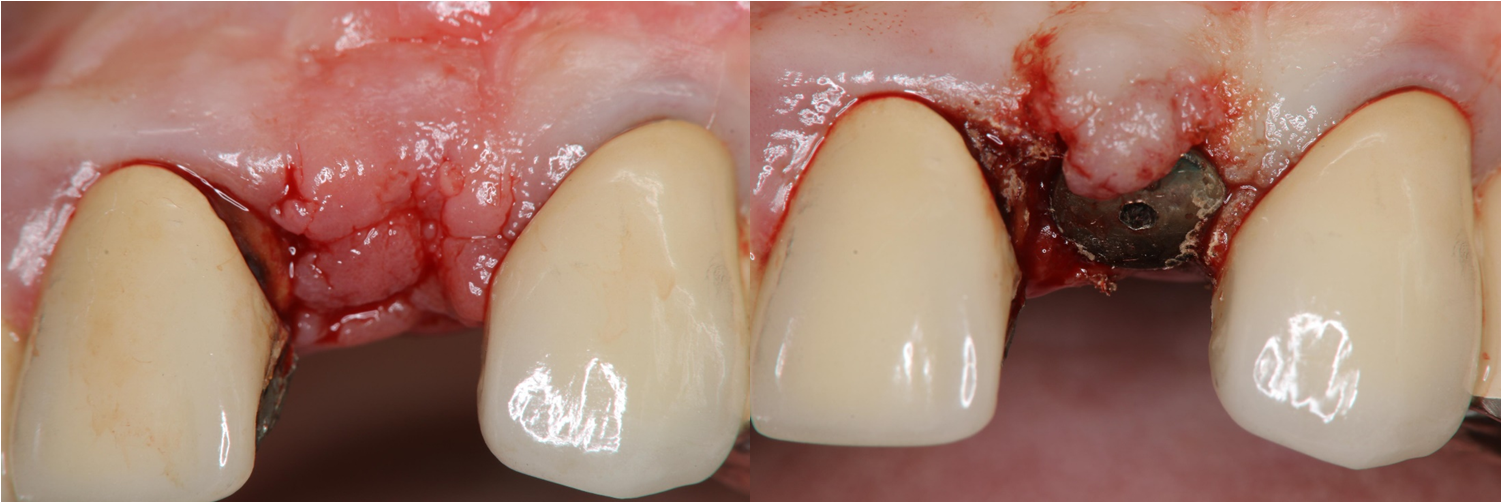

局部拔牙與立即植牙

植牙後,電腦斷層檢測